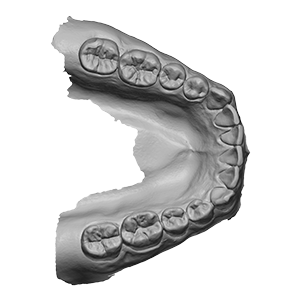

Unterkiefer–Scan

Unterkiefer–Scan

Unterkiefer–Scan

„Viade models by Trios LowerJawScan.stl“